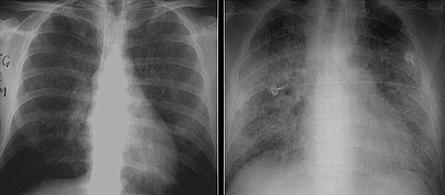

These chest radiographs are of two patients. Both show ground glass opacities. The left X-ray shows a much more subtle ground-glass appearance while the right X-ray shows a much more gross ground-glass appearance mimicking pulmonary edema.[6]

High-resolution computed tomography (HRCT) showing ground-glass attenuation with a geographic or mosaic distribution.[6]

HRCT of cysts of pneumocystis pneumonia. These are usually multiple and bilateral, but range in size, shape and distribution.[6]